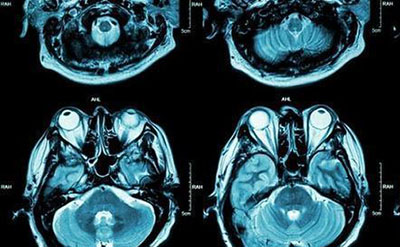

人类大脑有多少个神经元细胞?科学家称人类大脑有着惊人的860亿个神经元,人的大脑皮层约含有1~2百万个柱,每一个柱内有10000个左右的神经元

科学家称人类的大脑是有着惊人的860亿个神经元的家园,每个细胞织带在每个可能的方向都有几个连接,形成了一个超级巨大的蜂窝网络,这就使我们有了思想和意识。

根据计算神经科学前沿杂志发表的研究报告,一个围绕蓝脑项目聚集的国际科学小组已经获得了神经科学领域从未达到的成果。这个团队设法在大脑中找到呈现多维宇宙的结构,揭示神经连接的第一个几何设计以及它们如何响应刺激。

科学家利用深入的计算机建模技术来了解人类脑细胞如何组织起来,以便进行复杂的任务。研究人员使用代数拓扑的数学模型来描述脑网络中的结构和多维几何空间。在研究中,发现所有结构是在同一时间形成的,它们以一个联合交织在一起,产生精确的几何结构。

瑞士洛桑的蓝脑项目神经科学家和导演亨利马克兰(Henry Markram):我们找到了一个我们从未想象过的世界。即使在大脑的小斑点中也有数千万的这些物体,起码有七个维度。在某些网络中,我们甚至发现了多达11个维度的结构。

如科学家所指出的,我们大脑内的每个神经元都能够以特定的方式与相邻的神经元互连,以形成具有复杂连接的对象。有趣的是,越多的神经元与集团联系在一起,那么更多的维度就被添加到对象中。使用代数拓扑,科学家们能够在虚拟大脑中建模,在计算机的帮助下产生多维宇宙的效果。